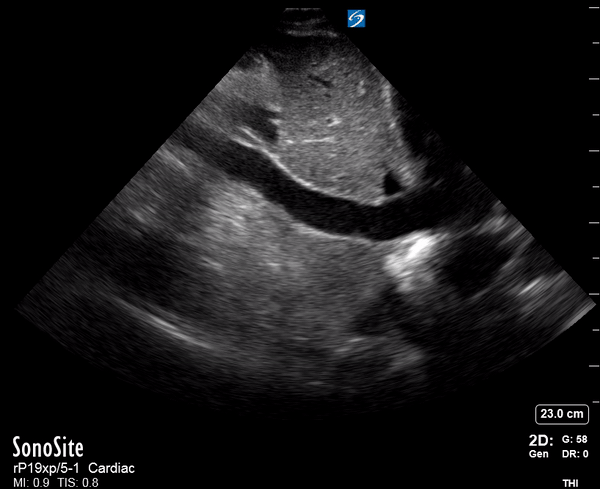

Effusion: is there a pericardial or pleural effusion?

Pericardial effusion is a continuum and can potentially evolve into haemodynamic collapse. Tamponade physiology is detectable earlier with ultrasound than with traditional physical examination, and it has been demonstrated that PoCUS improves mortality in penetrating cardiac trauma. Timely and accurate diagnosis is, therefore, vital.

THE VIEWS

The subxiphoid view is the most reliable for detecting pericardial effusion. Still, it is ideal to obtain different views not to miss a focal effusion as small amounts of fluid can lead to tamponade physiology. Tamponade does not link strictly to the size of the effusion, but correlates more with the speed of onset, causes, and haemodynamic effects.

PITFALLS & PLEURAL EFFUSIONS

A common error is to confuse a pericardial fat pad with effusion. Fatty tissue has a heterogeneous echotexture, moving in coordination with the myocardium, and it cannot be tracked around the heart, especially posteriorly and to the apex. Another pitfall is misinterpreting a pleural effusion as a pericardial effusion. However, they can be differentiated by their relationship to the descending aorta. Pericardial effusion may be seen between the aorta and the LV free wall, whereas pleural effusions are posterior to the descending aorta. Lastly, other causes, namely hypovolaemia and large pleural effusions, can cause RA and RV collapse.

CARDIAC TAMPONADE

Progressively rising pressure translates into evolving tamponade, and this accompanies a series of ultrasound findings:

Initially, the RA collapses during ventricular systole (closed AV valves).

Followed by RV collapse in ventricular diastole (open AV valves).

Ultimately leading to LV collapse.

In addition, the presence of a non-collapsible, plethoric IVC is one of the most sensitive signs of tamponade, and a finding easy to visualise. Conversely, a pericardial effusion in a haemodynamically stable patient with a collapsible IVC is unlikely to represent tamponade.